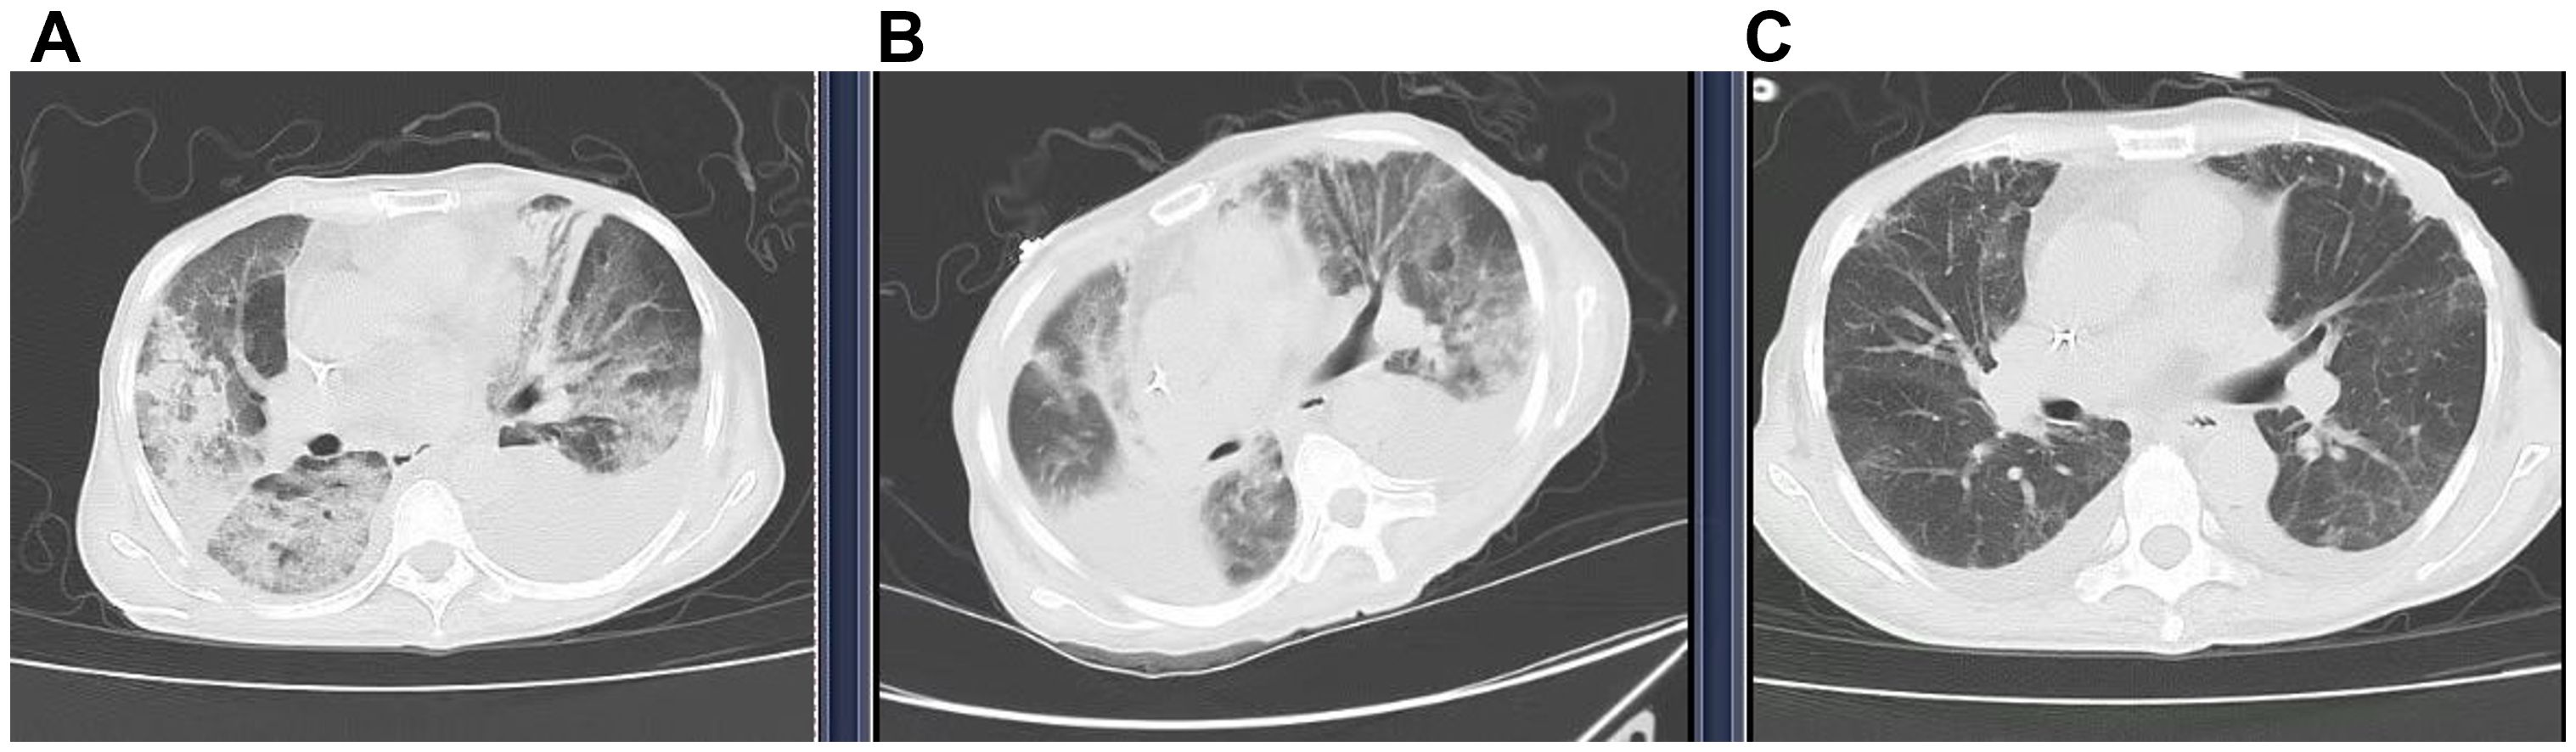

On November 28, 2024, she experienced sudden chest tightness and shortness of breath, with peripheral blood oxygen saturation (SpO2) of 50-70% on room air. Fine moist rales were auscultated in the upper and middle lung fields. Bedside ultrasound showed large bilateral pleural effusions, atelectasis, normal cardiac systolic function, and no signs of thrombosis. No significant abnormalities were found on urgent laboratory testing, including procalcitonin, D-dimer, NT-proBNP, and troponin T levels (Table 2). High-resolution chest CT (≤1.5mm thick, Figure 2A) showed diffuse patchy lesions in both lungs with uneven density and unclear edges, and bilateral pleural effusions (moderate on the left, small on the right. Based on the exclusion of alternative diagnoses (infection, pulmonary embolism, and heart failure) through the above workup, along with a history of T-DXd exposure, characteristic clinical features, and supportive CT imaging, a definitive diagnosis of interstitial pneumonitis was made.

CT scans of lungs labeled A, B, and C showing varying degrees of abnormalities. Image A displays significant opacities and consolidation, Image B shows moderate opacities, and Image C has clearer lung fields with minimal opacities.

Figure 2. Computed tomography (CT) showed the transition of ILD. (A) (29 Nov 2024) New diffuse bilateral patchy opacities with heterogeneous attenuation and ill-defined margins. Increased bilateral pleural effusions (moderate left, small right). (B) (5 Dec 2024) Diffuse bilateral opacities with heterogeneous attenuation, partial resolution (RML, left lung) but progression (RUL, right upper lobe). The right pleural effusion has increased and is partially encapsulated, whereas the left effusion has decreased slightly. (C) (11 Dec 2024) Significant resolution of bilateral diffuse opacities and reduction of bilateral pleural effusions.

A bedside right thoracentesis was performed to drain pleural effusion, and symptoms improved slightly after intravenous infusion of 80 mg methylprednisolone. Oxygen supplementation via a non-rebreather mask at 15 L/min stabilized her SpO2 between 94% and 99%. However, despite receiving a three-day course of methylprednisolone (80 mg q12h, from November 29 to December 1, 2024) for anti-inflammatory purposes, the patient continued to experience recurrent chest tightness and decreased SpO2. Then she was referred to our department with Grade 4 ILD (Diffuse Alveolar Damage/DAD pattern on CT) and life-threatening respiratory failure (NCI-CTCAE v5.0). Accordingly, the treatment was escalated to high-dose methylprednisolone (250 mg every 12 hours for 4 days, from December 2 to December 5) and intravenous immunoglobulin (20g daily for 3 days, totaling 1g/kg, from December 2 to December 4). To manage the left pleural effusion, a therapeutic thoracentesis was performed. Following three days of high-dose glucocorticoid and intravenous immunoglobulin pulse therapy, the patient maintained stable peripheral oxygen saturation (100%) on 10 L/min non-rebreather mask. However, repeat chest CT (5 December 2024, Figure 2B) demonstrated diffuse patchy opacities in both lungs with heterogeneous attenuation and ill-defined margins. Comparative assessment revealed partial resolution in the right middle lobe and left lung, but mild progression in the right upper lobe. Methylprednisolone was tapered to 55 mg q12h, and low-dose cyclophosphamide (50 mg qd) was added. Following six days of low-dose cyclophosphamide combination therapy, the patient demonstrated marked symptomatic improvement with resolution of chest tightness, maintained SpO2 of 100% on 4 L/min nasal cannula, and improved mobility in bed. A repeat chest CT (11 December 2024, Figure 2C) revealed bilateral diffuse patchy opacities with heterogeneous density and ill-defined margins, which had significantly decreased in size compared to prior imaging. Methylprednisolone was further reduced to 45 mg q12h. On December 13, the patient began oral prednisone with a slow dose reduction. She was discharged on December 16 with stable vital signs and instructions for outpatient follow-up. Following discharge, the patient continued oral cyclophosphamide at a constant dose and prednisone (with a slow tapering regimen starting at 35 mg twice daily and reduced by 20 mg per week) until both medications were discontinued on January 10, 2025, but declined serial complete blood count monitoring and prophylactic trimethoprim-sulfamethoxazole (TMP-SMX) for Pneumocystis jirovecii pneumonia (PJP) prevention. At 30-day follow-up, she maintained an oxygen saturation of 100% on 2 L/min nasal cannula; however, she exhibited marked cachexia, suggesting possible progression of her underlying malignancy. The specifics of the treatment protocol, including dosage and duration, are summarized in Table 3.